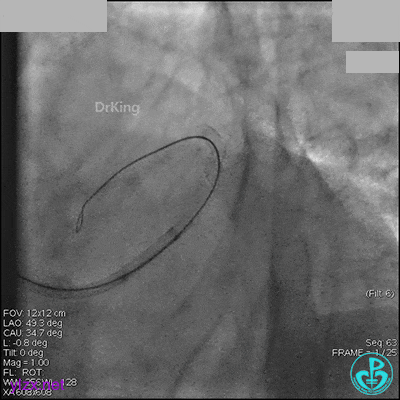

AL 1.0指引导管到位,简单短时尝试导丝不能顺利通过前降支或回旋支病变。改变策略处理右冠脉病变,计划植入2枚支架。AL指引导管到位,Sion blue导丝到达右冠脉远端。导丝通过后1.5mm及2.5mm球囊14~16atm充分扩张中段病变。

右冠脉中段充分扩张后欲植入3.5×38mm支架时,支架难以通过中远段扭曲处,且指引导管、导丝弹出飞扬。反复尝试导丝重新到达右冠脉远端时通过不顺利,局部造影剂滞留,远端血流接近3级。